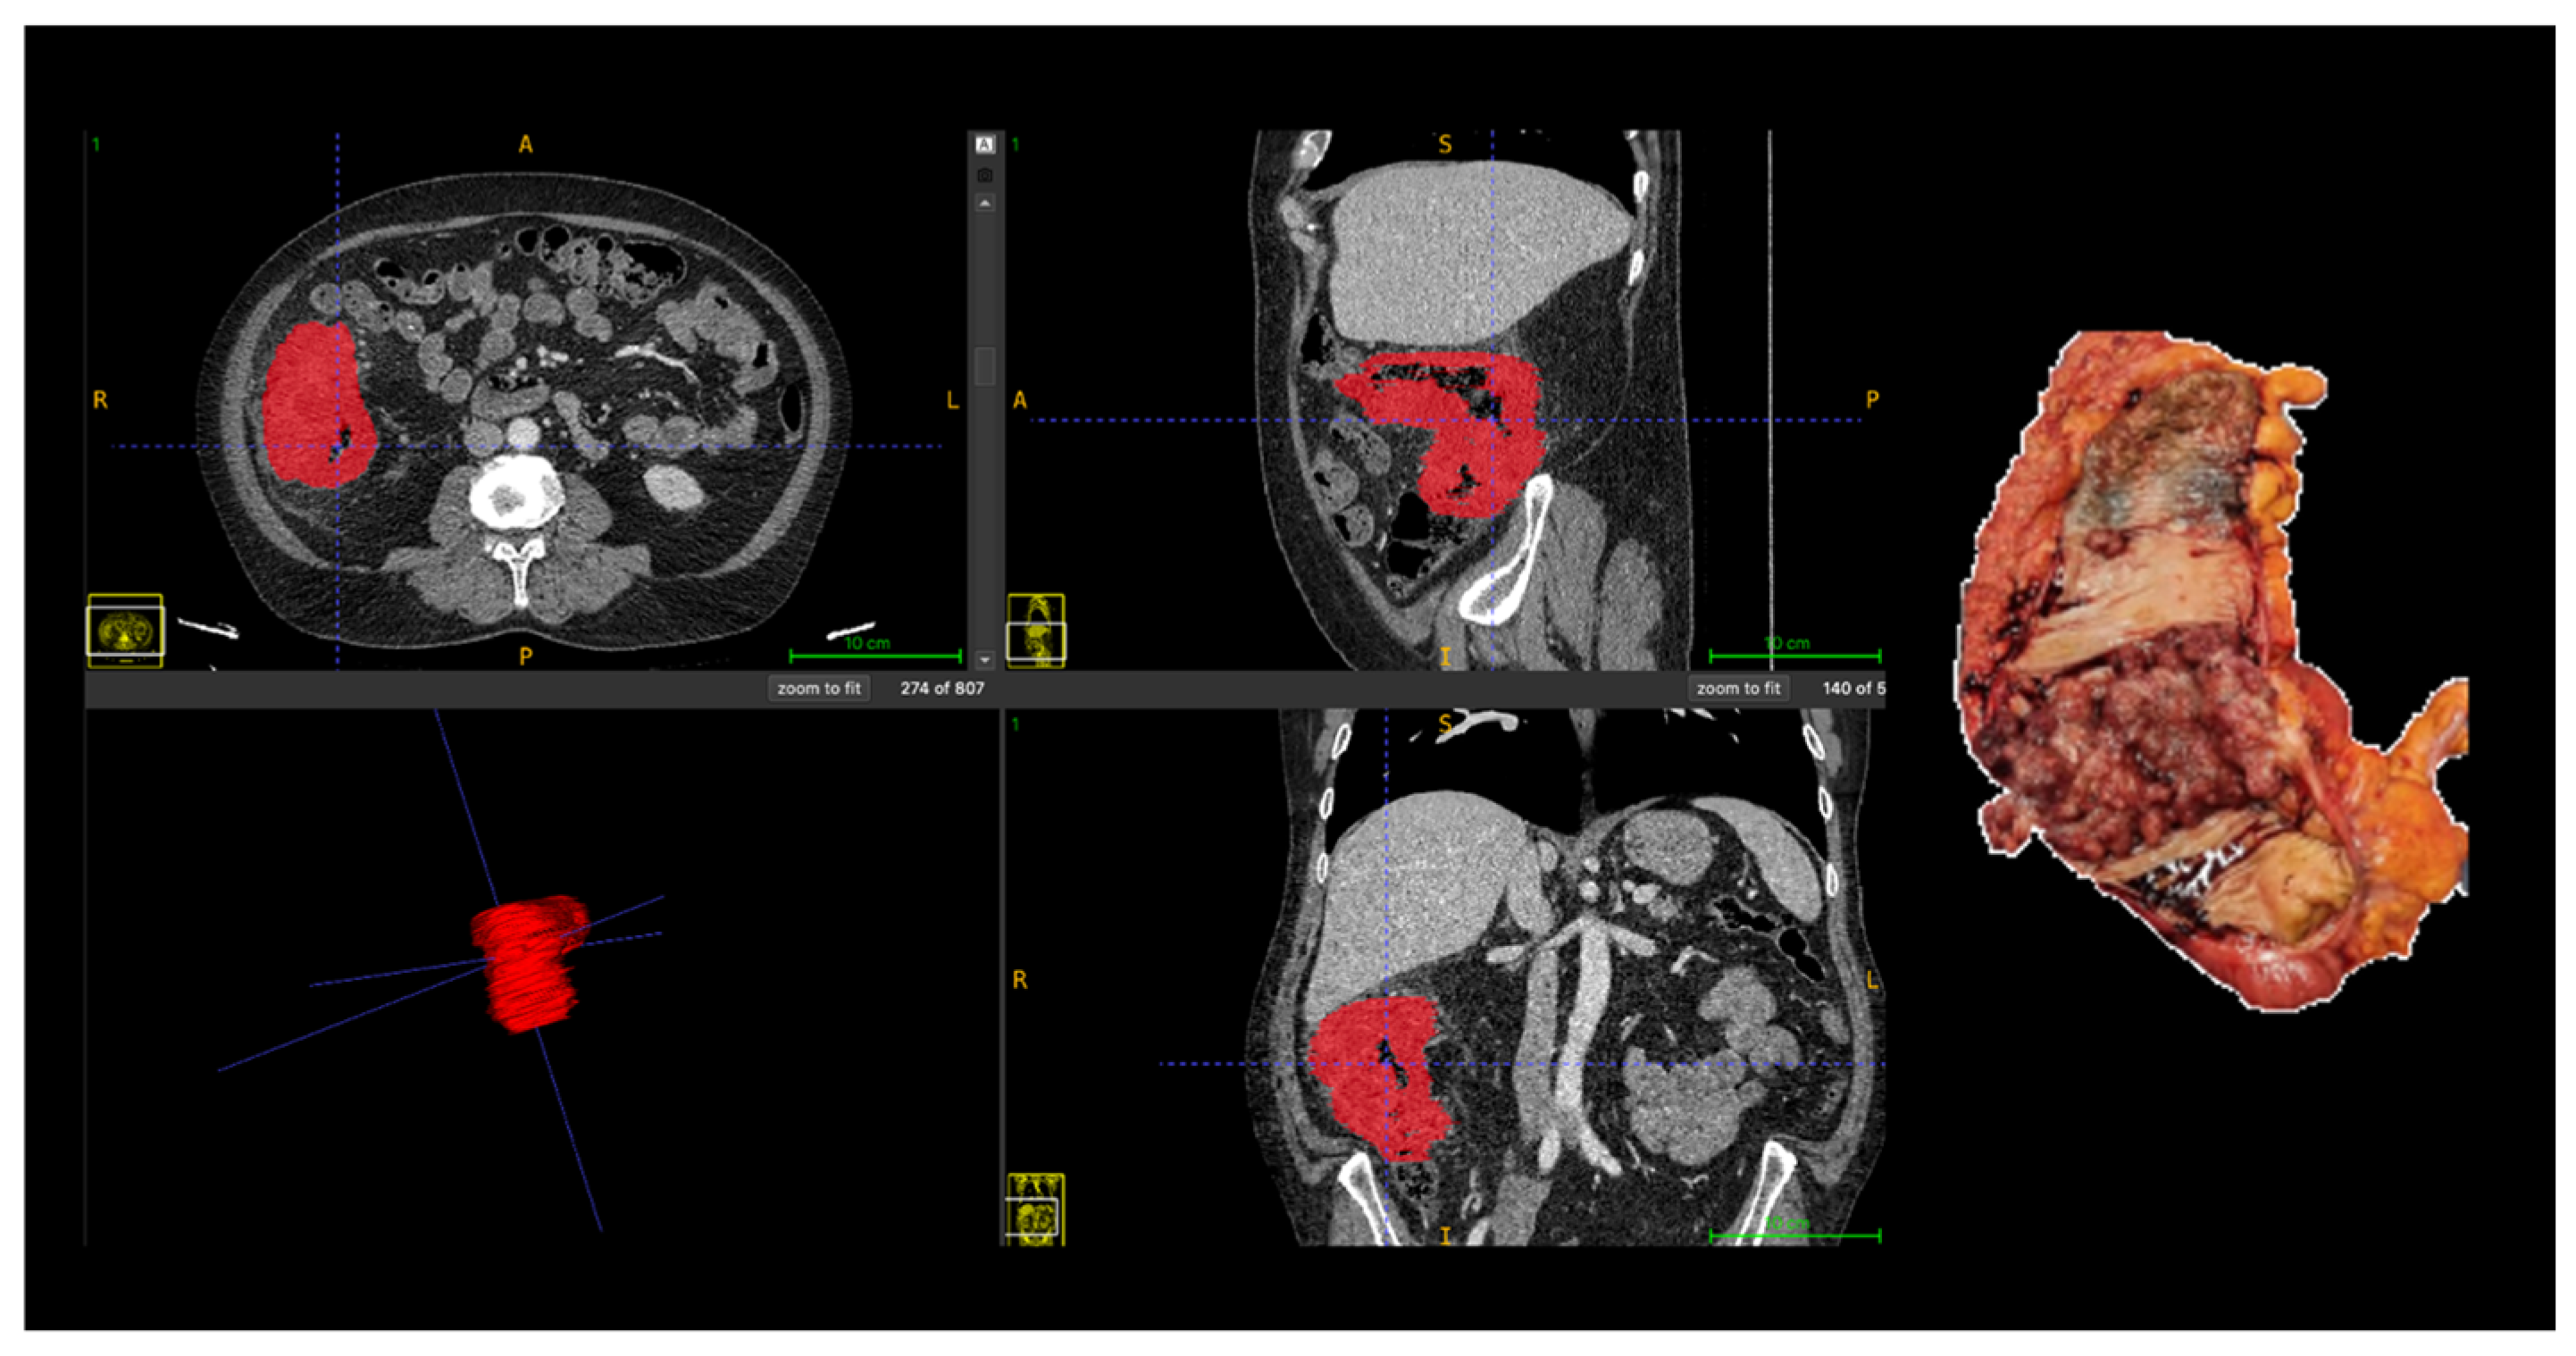

All segmentations were performed following a standardized institutional protocol by a single radiologist, using multiplanar visualization in ITK-SNAP software (version 3.8; www.itksnap.org) to ensure anatomical consistency. In cases with ambiguous tumor margins or complex anatomy, segmentations were supervised and reviewed by a senior abdominal radiologist to ensure anatomical accuracy. The region of interest (ROI) was delineated along the tumor boundary on three consecutive axial slices that best represented the lesion. Areas of intraluminal air, necrosis, vascular structures, and pericolic fat were carefully excluded from the contours (Figure 1).

Manual segmentation of colorectal tumor (Patient 18) on portal venous phase CT and corresponding surgical specimen. The region of interest (ROI) was manually delineated (in red) on three consecutive slices using ITK-SNAP software, excluding intraluminal air, necrosis, vessels, and pericolic fat. Abbreviations: ROI, region of interest; CT, computed tomography; A, anterior; P, posterior; R, right; L, left, S, superior; I, inferior.

Representative case illustrating the correspondence between radiomics-based tumor segmentation on contrast-enhanced CT and the corresponding pathological anatomy are shown in Figure 3.

Correlation between radiomics-based tumor segmentation on contrast-enhanced CT and pathological anatomy in advanced (T4) colon cancer. Axial, coronal, and sagittal CT images with manual tumor segmentation (red); Three-dimensional rendering of the segmented tumor; Corresponding gross surgical specimen. Abbreviations: A, anterior; P, posterior; R, right; L, left, S, superior; I, inferior.